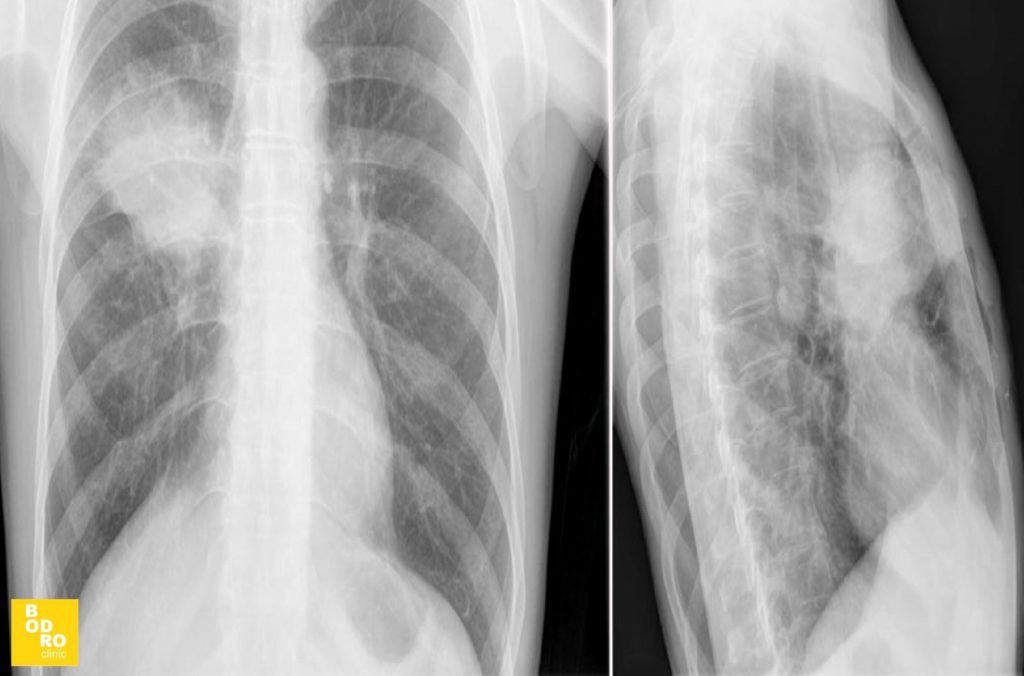

Рентгенографія органів грудної клітки (ОГК) – це неінвазивний метод діагностики, який дозволяє оцінити стан легенів, серця, судин та кісткових структур грудної клітки. Дослідження широко застосовується для виявлення різних захворювань дихальної та серцево-судинної систем.

- Пацієнт стає перед рентгенівським апаратом, зазвичай у двох проекціях – прямій та бічній.